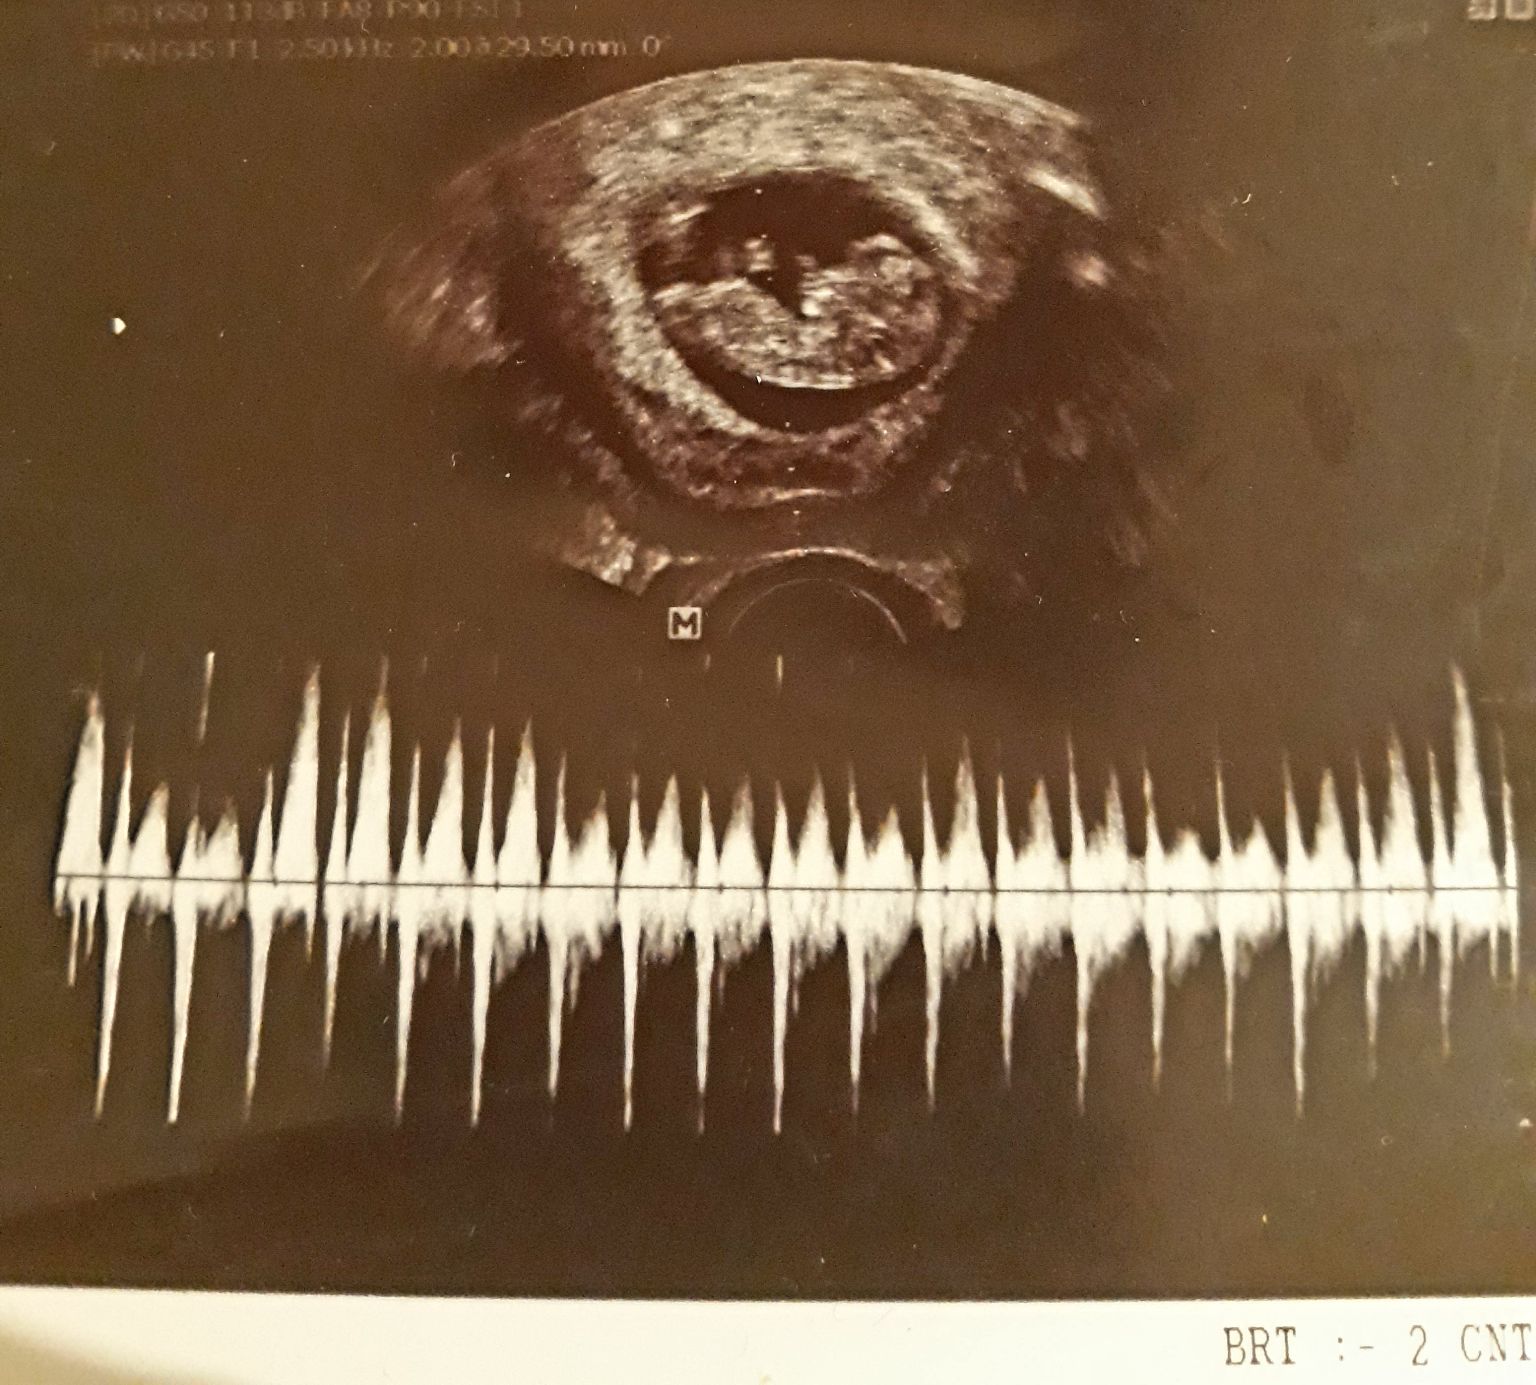

Daha önce de belirtildiği gibi, hem erkek hem de kız fetusların gelişme aşamalarında genital bir tüberkül vardır. Bu genital tüberkül bir nub olarak adlandırılır.Nub Teorisini kullanarak bebeğinizin cinsiyetini belirlemek, büyük oranda ultrason resmine bağlıdır. Bu, nub resminin sonucu belirlemeniz için mükemmel olması gerektiği anlamına gelir.

12-14 hafta ultrason taramasını yaptıktan sonra, Cinsiyet Uzmanları genital tüberkülün görünürlüğünü kontrol edecektir. Görünürlüğü, bebeğin pozisyonu, kese içindeki amniyotik sıvı miktarı, karın duvarının kalınlığı, tarama kalitesi ve / veya çözünürlüğü etkilenebilir.

Gebeliğin 9. haftası fetusun bacaklarının arasın da küçük bir çıkıntı görülür. Gebeliğin 12. ve 14 haftası bu topak çıkıntı nın açısı değerlendirilerek , cinsiyet tahmini yapılır. Çıkıntı kızlar da 30 derecenin altın da ve düzdür erkekler de ise 30 derecelik açıdan büyüktür.

Nub teorisin de cinsiyet belirleyen uzmanlar 12- 14 . haftalar da genital tüberkül görünürlüğü kontrol edecektir.Bebeğin pozisyonu , kese içinde amniyotik sıvı miktarı, karın duvarı, tarama kalitesi veya çözünürlük kalınlığı etkilenebilir. Cinsiyet belirlemek için, Cinsiyet Uzmanları aşağıdaki ölçütleri kullanmaktadır.

Görünürlük , omurga ile ilgili genital tüberkül açısı , Gölgeler ve erkek belirteçler ve topak çevreleyen ucu , Gebelik yaşına göre uzunluğu da dahil olmak üzere, şekil.. Nub teorisi ile cinsiyet belirleme de tarama omurga görüntüleme ve buna özü ilişkisini sağlamak için, profil görünümünde olmalıdır.